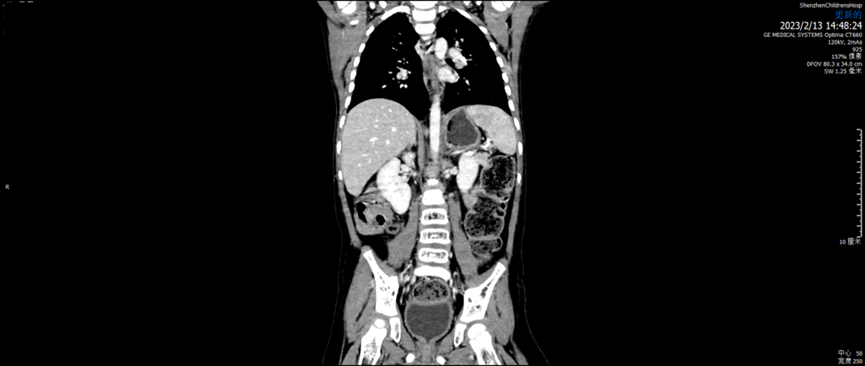

2023.02.13

腹膜后NB术后复查:未见异常。